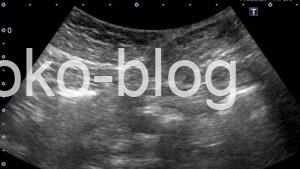

おや、皮下に何かが…

拡大してみました。うーん?